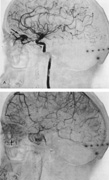

From 85% to 90% of AVMs are in the supratentorial compartment and are supplied primarily by the carotid circulation (Figs. 7 and 8). The remainder are supplied by the vertebrobasilar system. The approximate frequency of location is as follows: frontal, 22%; temporal, 18%; parietal, 27%; occipital, 5%; and deep intraventricular or paraventricular, 18%. The intracerebral site of the malformation does not necessarily indicate that there will be signs referable to that area simply from the mass effect of the malformation. Clinical features primarily result from subarachnoid hemorrhage or intraparenchymal hemorrhage with hematoma formation.

Fig. 7. Supratentorial arteriovenous malformation in a 28-year-old woman with a history of focal motor seizures for many years and a recent subarachnoid hemorrhage. A: Lateral projection carotid arteriogram demonstrating a huge deep hemispheral arteriovenous malformation. B: Frontal projection. C: Fundus photograph showing anomalous tortuous vasculature in each eye. No retinal arteriovenous shunt was detectable.

Fig. 8. Multiple supratentorial arteriovenous malformations (AVMs). A: Lateral projection of left carotid arteriogram shows dilated afferent artery (solid arrow) feeding the right hemispheric parietal AVM (open arrow). B: Right carotid injection fills a second, more posteriorly located, parietooccipital AVM (open arrow), which drains immediately to markedly dilated cortical veins (curved arrow).